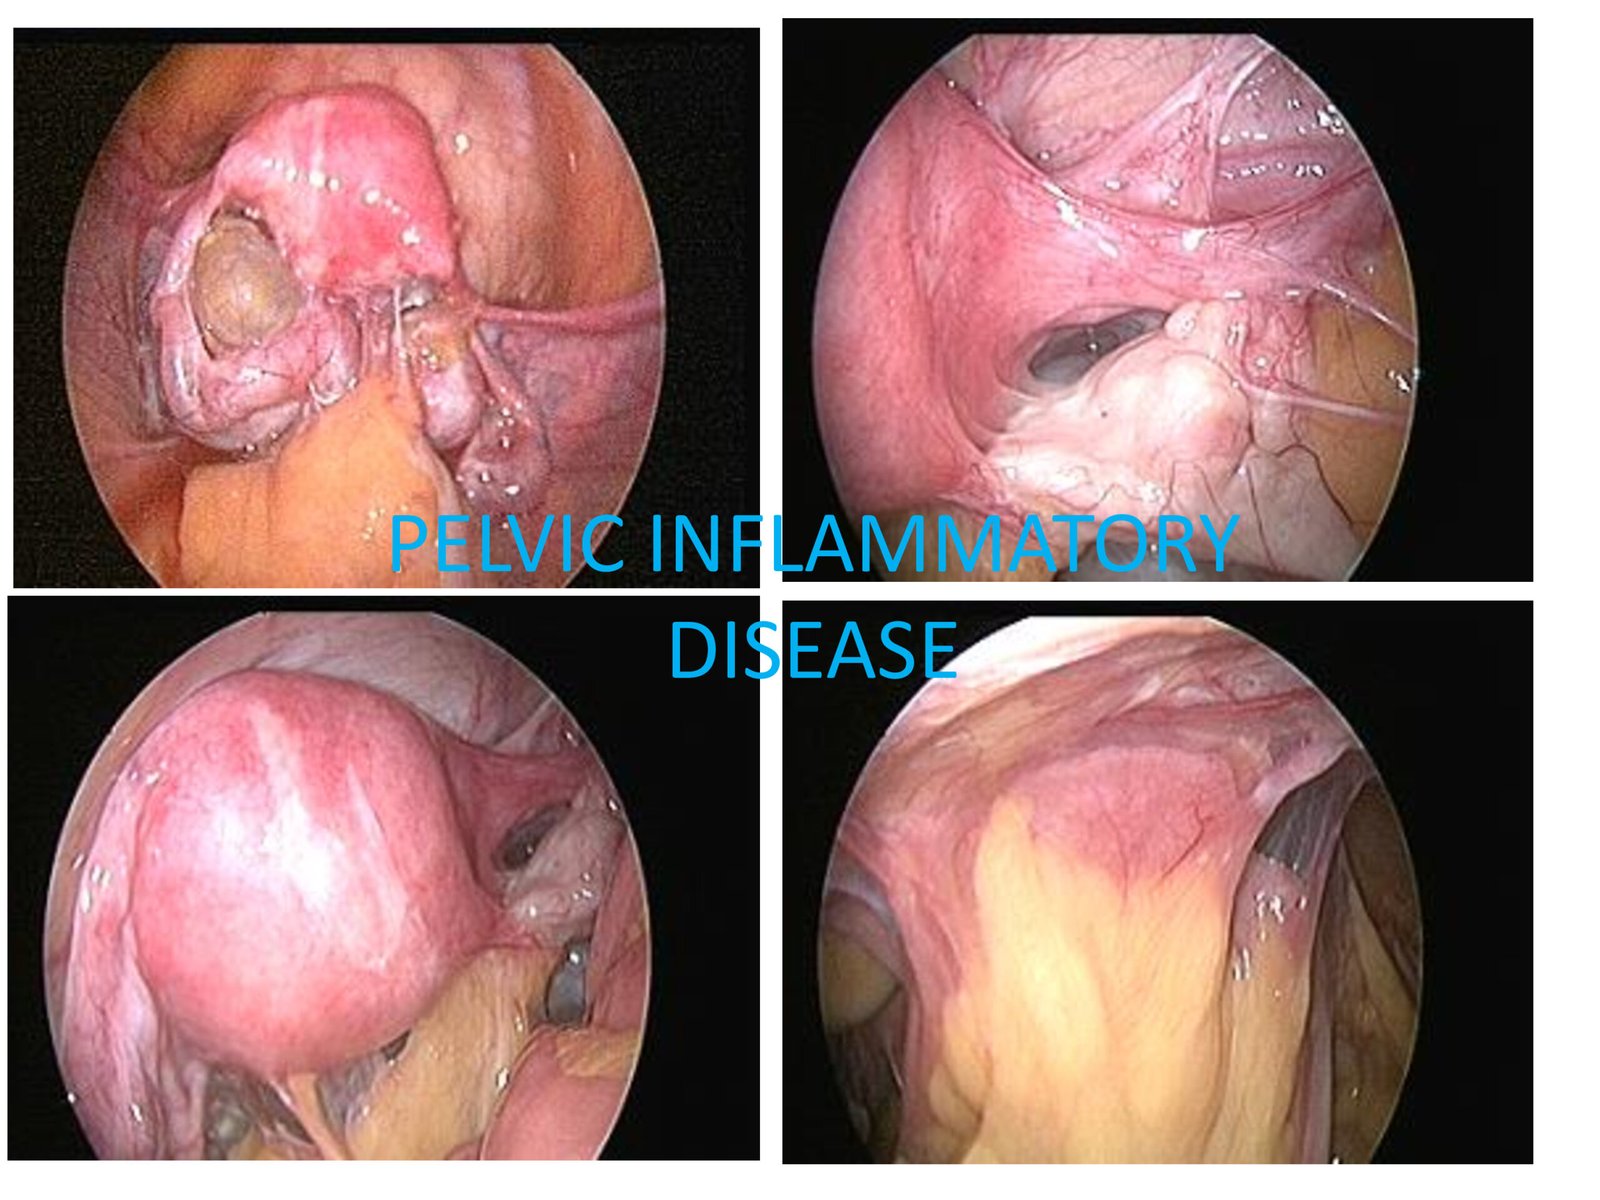

PID can be defined as infection of the upper genital tract involving the cervix (mouth of the uterus), uterus, fallopian tubes, parametria (sides of the uterus and ovaries).